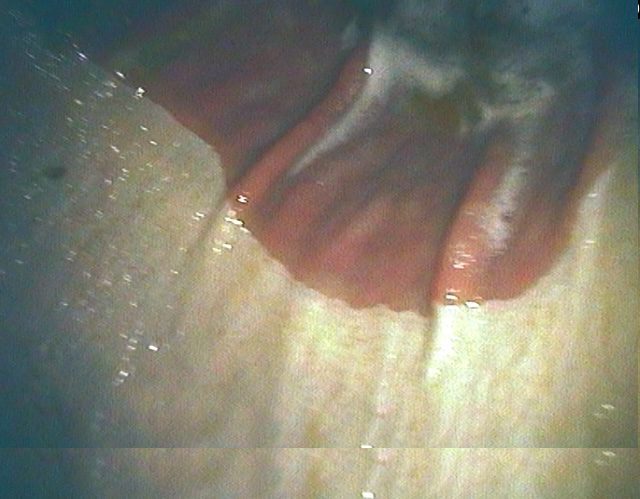

The Normal Stomach

Normal Greater Curvature

Normal Lesser Curvature